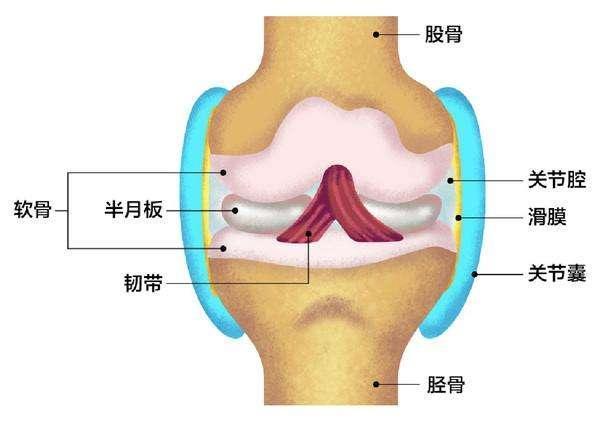

膝关节疼痛严重者不能走路的大有人在,而目前膝关节疼痛已经成为老百姓日常生活中多发的疾病。膝关节主要是由大腿骨,胫骨,腓骨以及膝盖骨等4部分组成。其中大腿骨以及胫骨是通过膝关节进行连接的,在他们中间有层关节软骨以及半月板起着重要的作用。另一方面,膝关节的关节囊内侧的滑膜层在不断的分泌润滑液,使得膝关节活动正常。

1,膝关节退化

膝关节退化一般多发生在中老年身上,随着年龄的增长,膝关节退化的速度也会越来越快。而膝关节退化导致膝关节软骨和半月板磨损加重,膝关节疼痛就会越来越严重,而一旦严重退化,那么膝关节软骨就有可能变得又薄又脆,容易引发一系列综合症。

2,膝关节损伤严重

说到膝关节损伤严重,这是很多人在日常生活中都有可能遇到的,如:剧烈运动,膝关节受伤等都会带给膝关节强大的冲击力,导致半月板损伤,膝关节处的连接骨之间韧带断裂,这种疼痛会逐渐加重,最后有可能疼的不能下地行走。